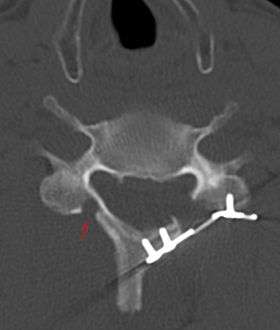

![]() CT scan of Laminoplasty of cervical vertebra | |

Laminoplasty is an orthopaedic/neurosurgical surgical procedure for treating spinal stenosis by relieving pressure on the spinal cord. The procedure involves cutting the lamina on both sides of the affected vertebrae (cutting through on one side and merely cutting a groove on the other) and then "swinging" the freed flap of bone open thus relieving the pressure on the spinal cord. The spinous process may be removed to allow the lamina bone flap to be swung open. The bone flap is then propped open using small wedges or pieces of bone such that the enlarged spinal canal will remain in place.